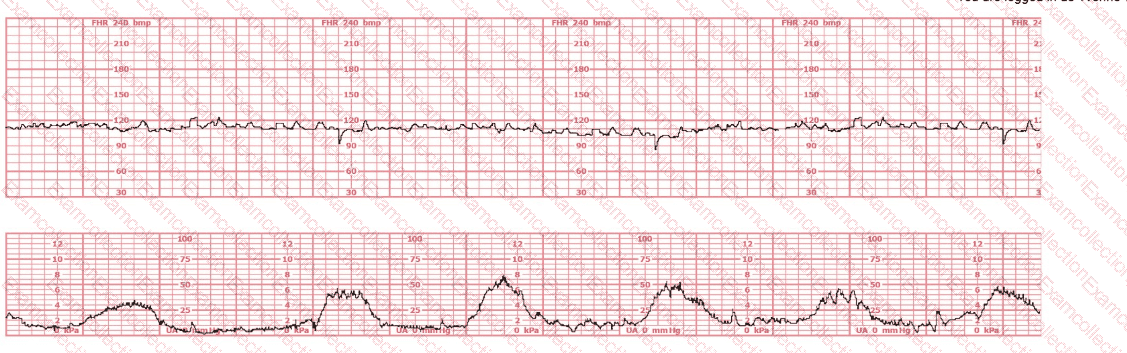

A woman at 38-weeks gestation is admitted to labor and delivery following a fall down the stairs three hours ago. She started feeling contractions in the ambulance. The fetal heart rate tracing shown is on initial evaluation and represents 25 minutes. This tracing is most consistent with a